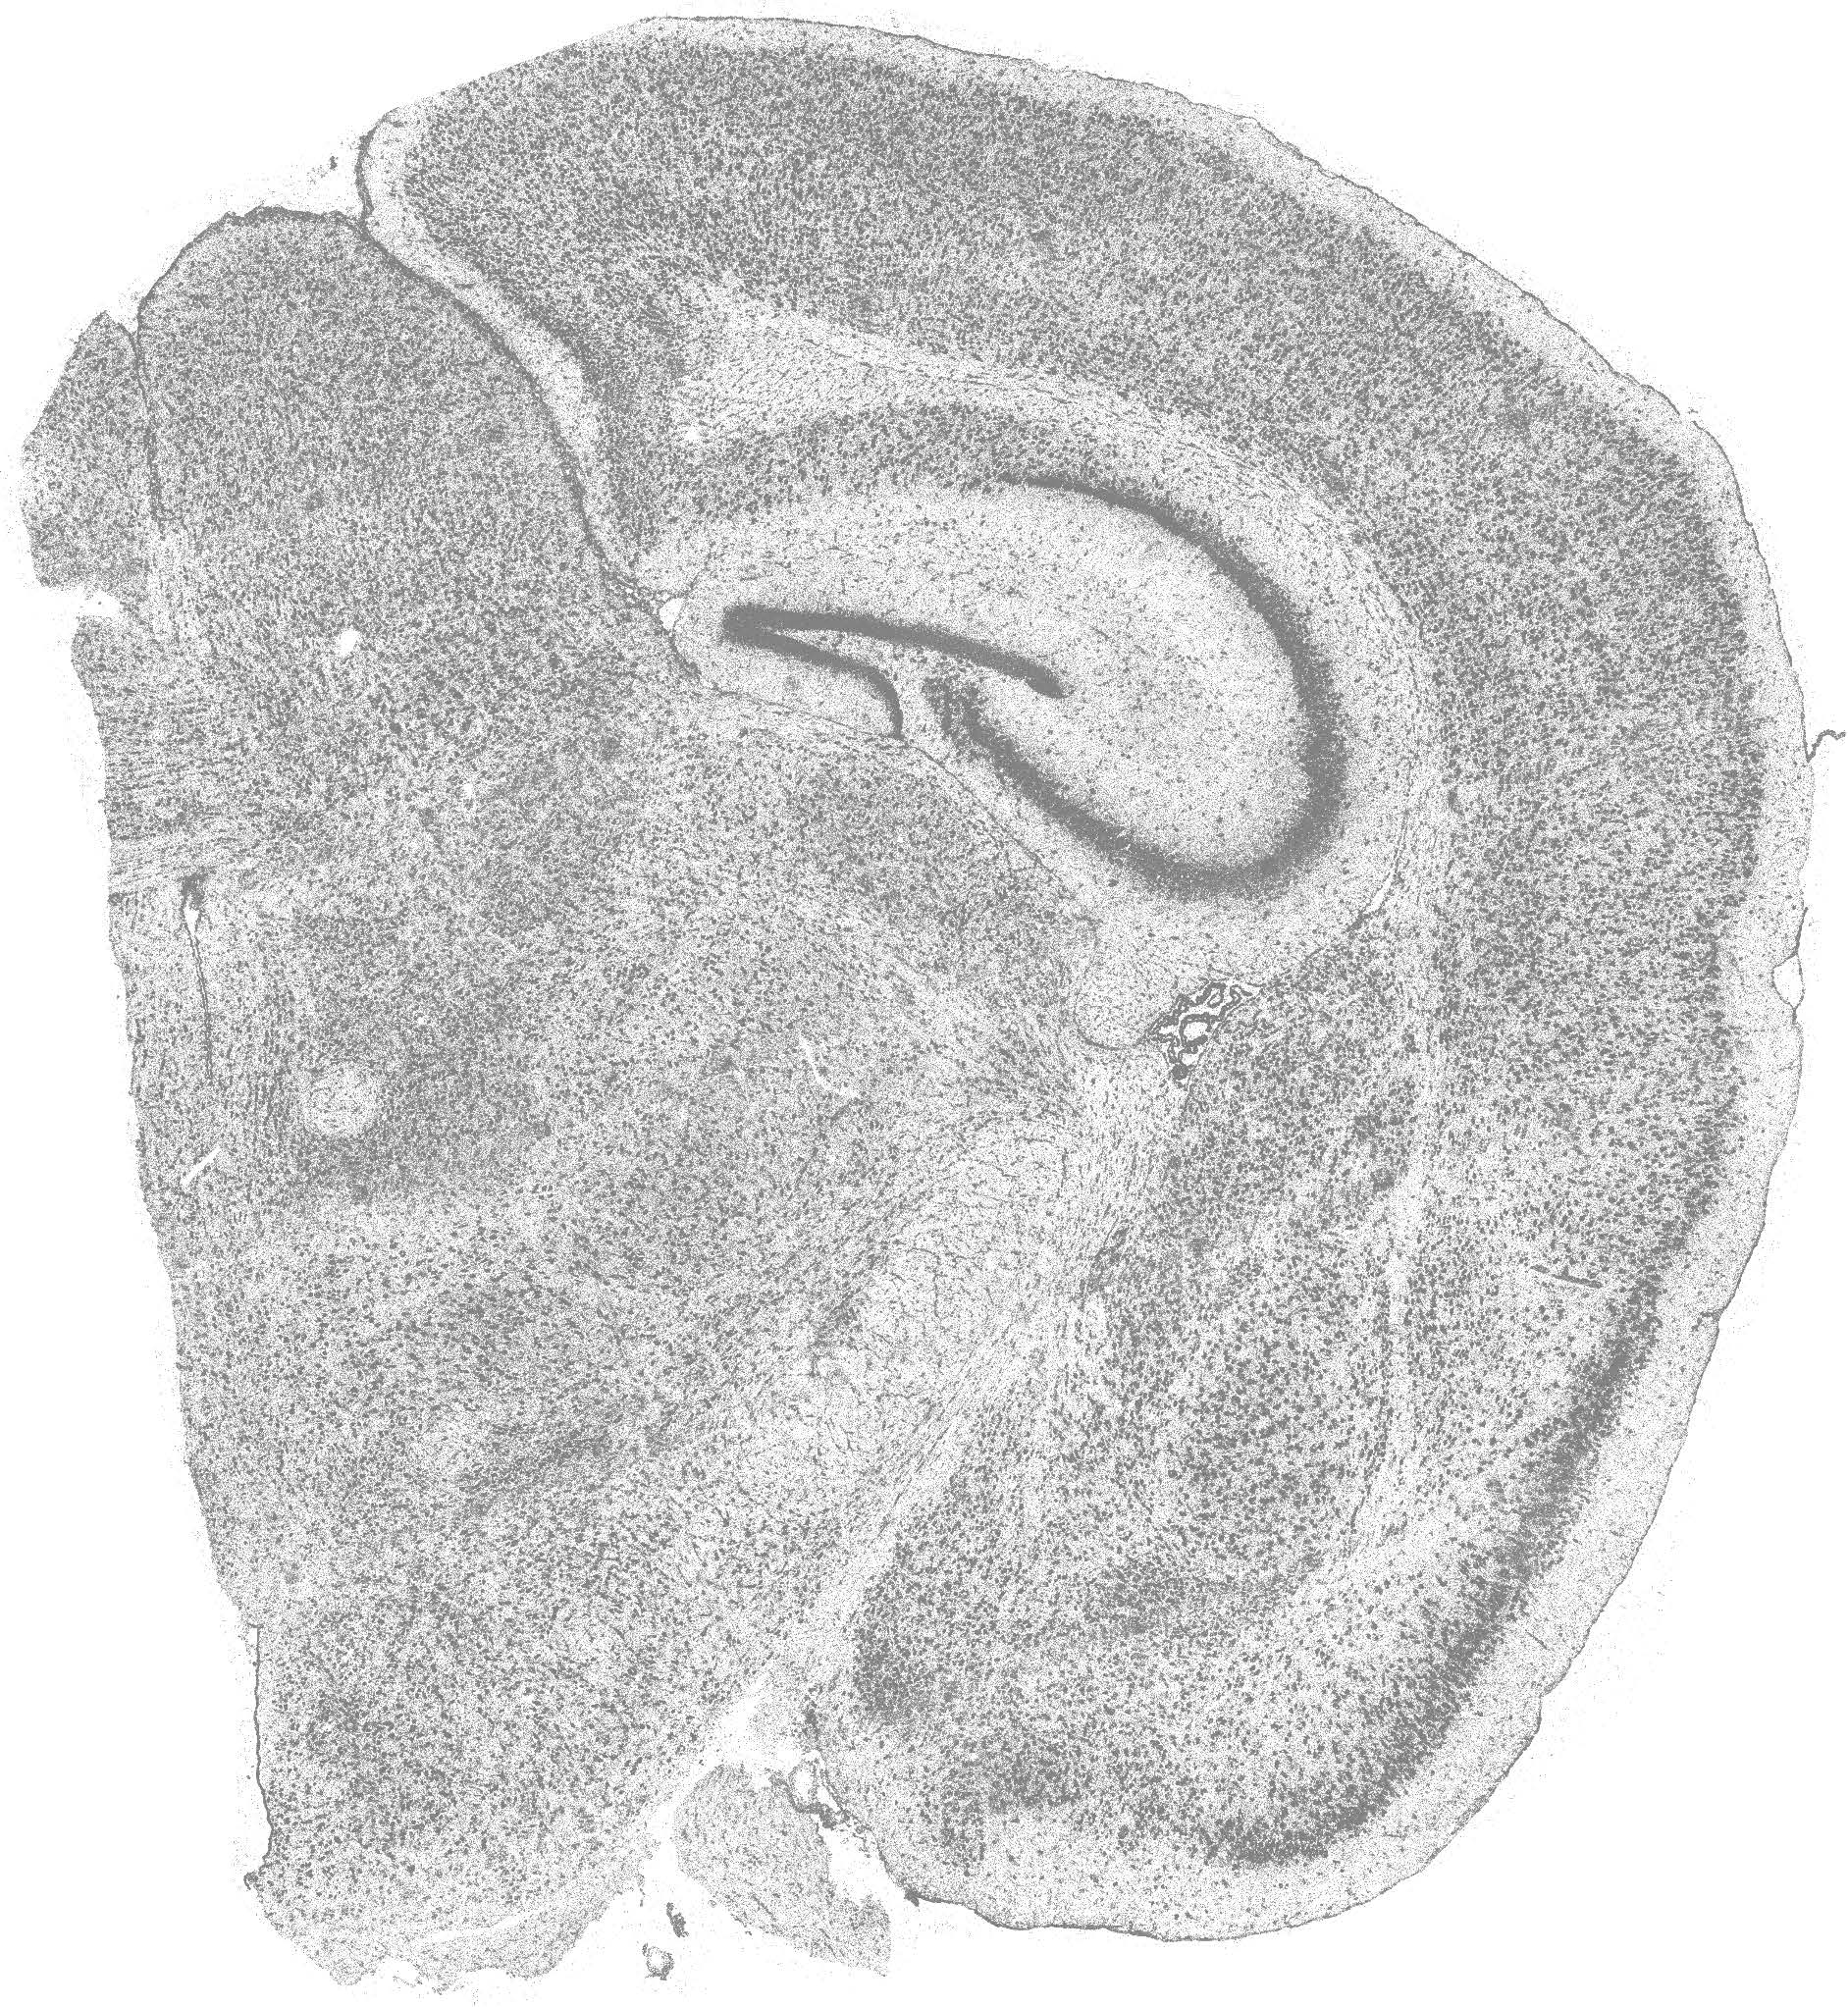

Xenium亚细胞组织原位分析技术结果展示